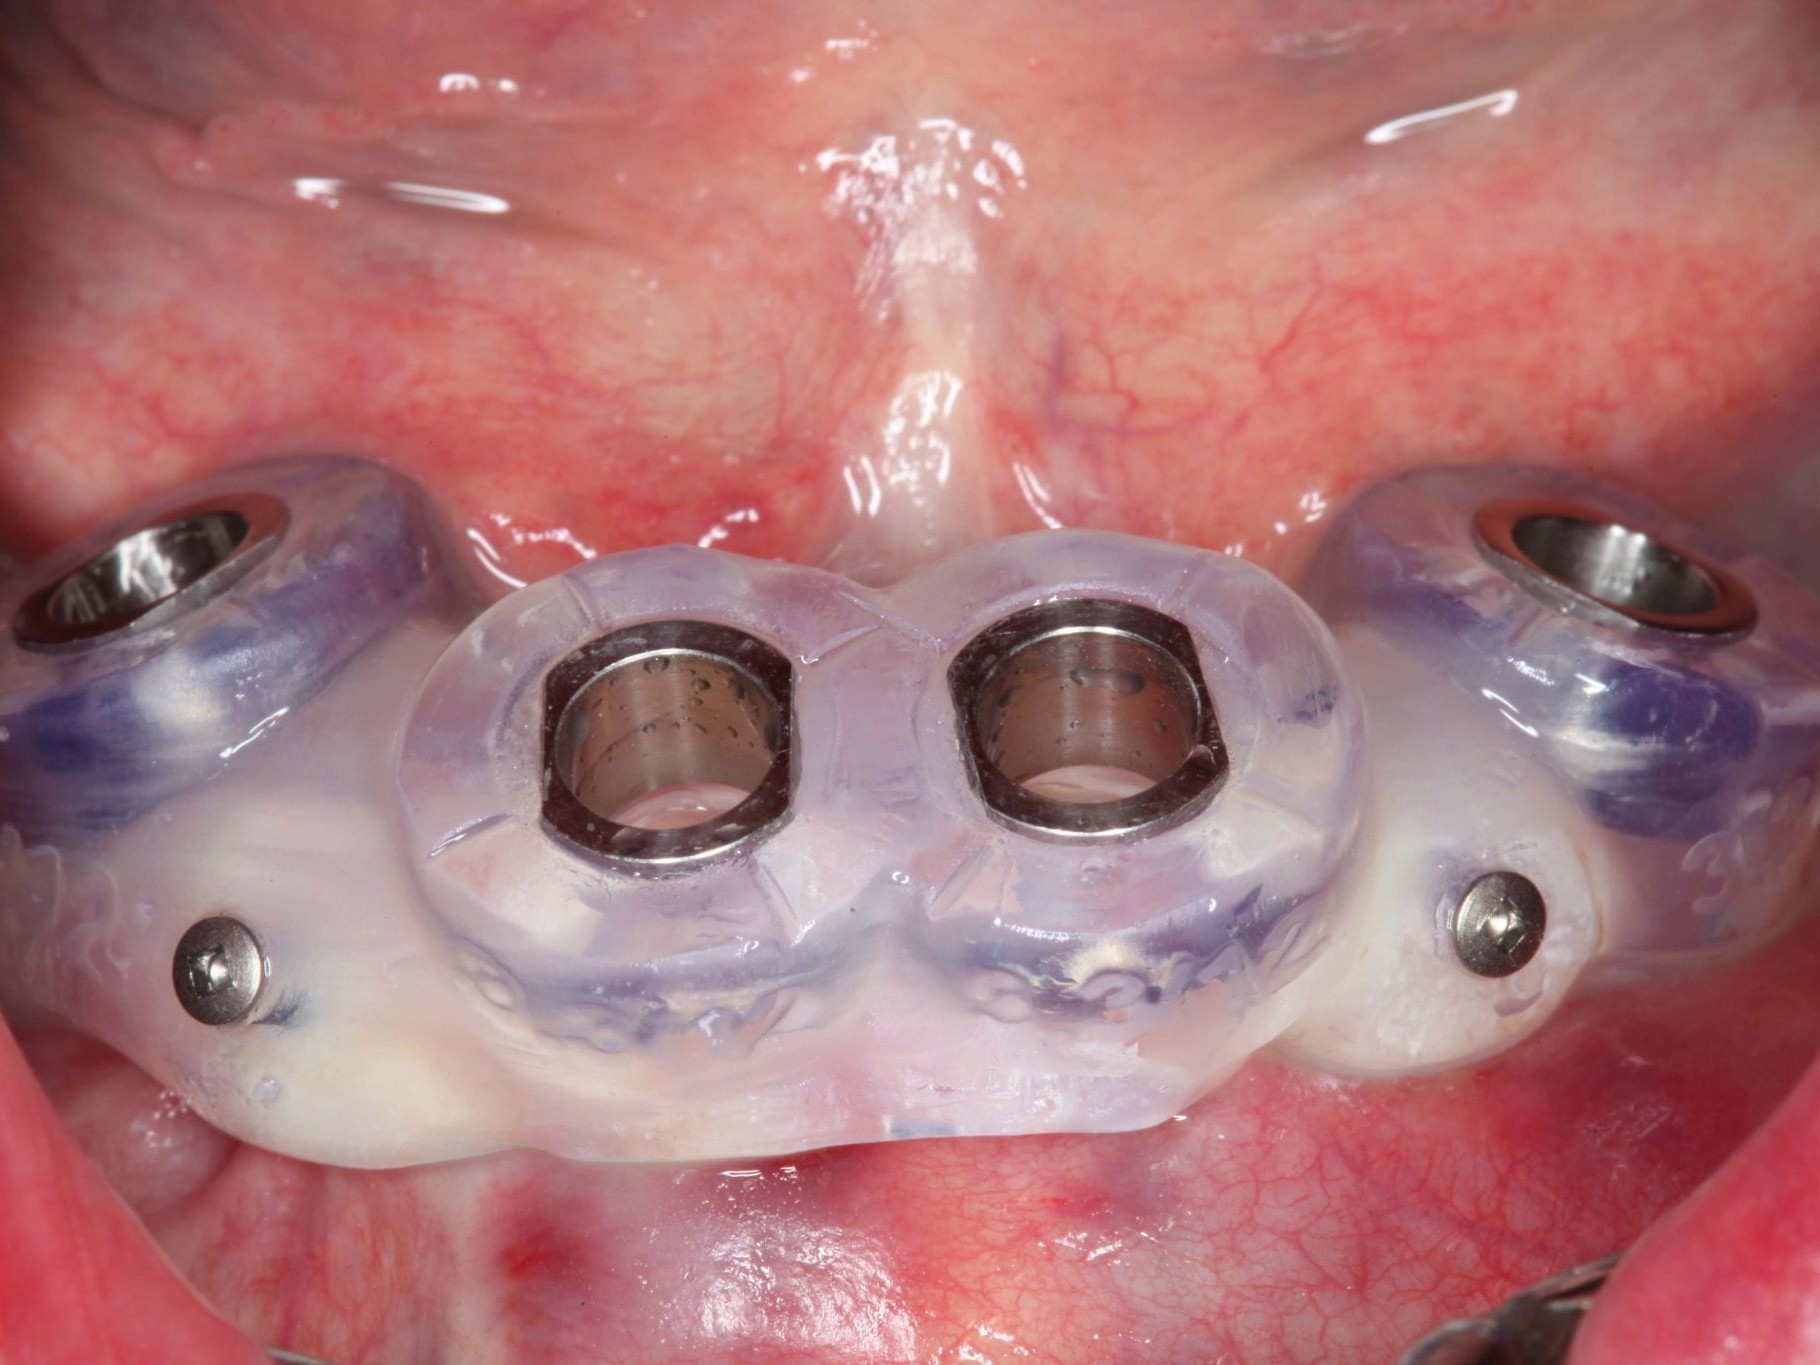

In Lokalanästhesie unter anästhesiologischem Standby mit intravenöser Antibiose mittels Clindamycin 600 mg 2mal/d wurde die Bohrschablone eingesetzt und mit Osteosyntheseschrauben fixiert (Abb. 8). Der Eingriff erfolgte nahezu flapless und somit transgingival. Nun erfolgte die Umsetzung des Straumann Hülse-in-Hülse-Konzeptes. Der Zylinder des Bohrlöffels wird in die an der Bohrschablone fixierten Hülse (Ø 5 mm) in den geplanten Regionen eingeführt. Für jeden Bohrerdurchmesser (Ø 2,2 mm und Ø 2,8 mm) ist ein entsprechender Bohrlöffel erhältlich. Jeder Bohrlöffel besitzt an seinen Enden Zylinder unterschiedlicher Höhe, die entsprechend chirurgischem Protokoll angewendet werden. Es wurden sämtliche Bohrstollen protokollgemäß aufbereitet (Abb. 9-11). Nach der Aufbereitung der Bohrstollen für die angulierten Implantate (Abb. 12-14) wurden die Straumann Bone Level Tapered Implantate (ø 3,3 mm) in regio 035 (Länge 10 mm) und 045 (Länge 12) gesetzt (Abb. 15). Abschließend wurden sämtliche Endpositionen der Implantate in regio 035 und 045 anhand der Lasermarkierungen am Übertragungsteil betreffend ihrer orovestibulären Ausrichtung exakt überprüft (Abb. 16). Nach Entfernung der Einbringhilfen und der Osteosyntheseschrauben konnte die Bohrschablone wieder entnommen werden. In regio 032 und 042 wurden nun die durchmesserreduzierten Straumann NNC (ø 3,3 mm Länge 12 mm) Implantate inseriert (Abb. 17, 18). Bei diesen Implantaten bedurfte es keiner Ausrichtung bezogen auf die orofasziale Ausrichtung. Hier musste die Insertionstiefe bezogen auf das NNC-Implantat beachtet werden (Abb. 19). Die NNC-Implantate wurden mit den entsprechenden Klebebasen versehen (Abb. 20). Danach wurden in regio 035 und 045 auf die Pro Arch Sekundärteile die dazugehörigen Retentionskappen (Abb. 21), die zur Vergrößerung der Oberfläche mit 120 μ Aluminiumoxyd abgestrahlt wurden, eingesetzt. Es erfolgte der typische Naht-Wund-Verschluss mit Einzelknopfnähten. Zum Abschluss erfolgte das prothetische Procedere mit der Eingliederung des Interimszahnersatzes in Okklusion (Abb. 22). Hierfür wurden die Retentionskappen und die Klebebasen mit dem Sofortprovisorium über ein selbsthärtendes fluoreszierendes kaltpolymerisierendes Paste-Paste-Kartuschensystem fixiert, dieser Zahnersatz extraoral versäubert (Abb. 23) und in der Mundhöhle refixiert (Abb. 24). Die Schraubenkanäle wurden mit Kunststoff verschlossen (Abb. 25). Abschließend erfolgte die radiologische Kontrolluntersuchung (Abb. 26).